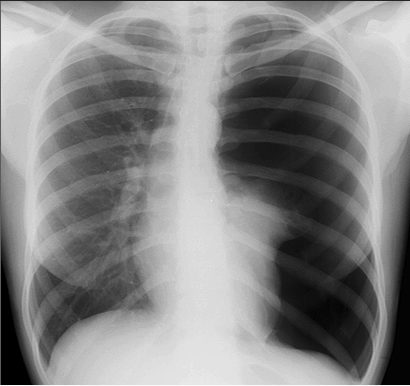

Pneumothorax

Tension pneumothorax